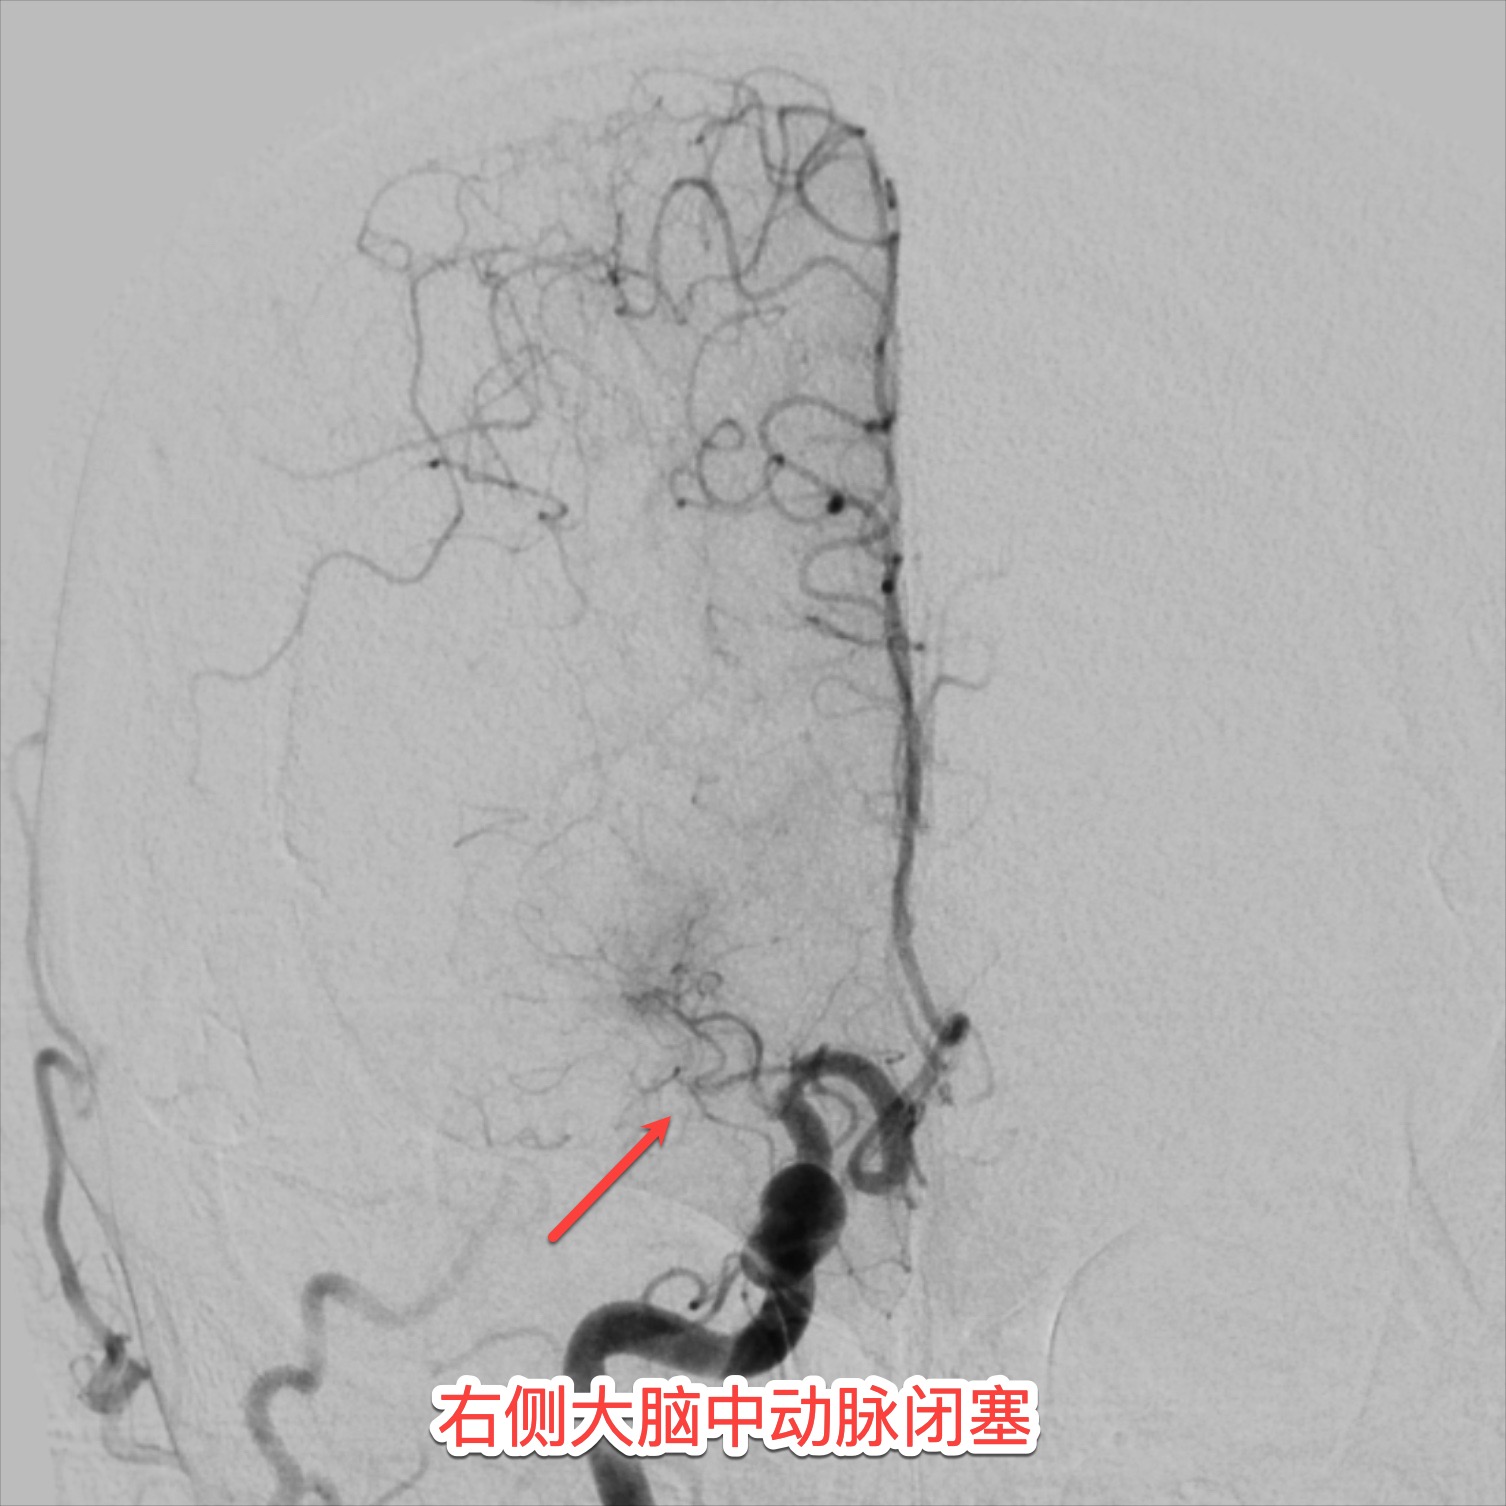

14:27,患者被推入导管室。介入科副主任医师王宁带领团队在DSA引导下精准穿刺,造影显示右侧大脑中动脉完全闭塞。“找到‘罪犯血管’了!”取栓支架如微型“捕网”般穿越重重血管,15:01,一条团块状暗红色血栓被完整取出,血流瞬间复通!从入院到血管再通,仅耗时3小时。